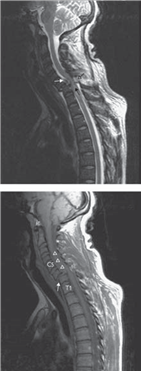

A 67-year-old man falls onto his face and presents with an abnormal neurological examination and neck pain.

What do you see?

This is a T2-weighted sagittal MRI scan demonstrating Grade 2 spondylolisthesis of C6 upon C7 with large disc protrusion. The spinal cord is compressed and there is intramedullary signal change, in keeping with oedema, from C6 to T1.

What is the most likely pattern of incomplete cord injury?

Central cord syndrome.

What are the clinical features of this injury and how would you manage the patient?

T here will be predominantly motor rather than sensory defi cit aff ecting the upper extremity more than the lower extremity. It is not unusual to see marked early neurological recovery in such cases, and where no spinal instability exists non-operative management is the standard of care. However, in patients who plateau with a functional disability in conjunction with image-proven cord impingement surgical decompression and stabilization should be considered.